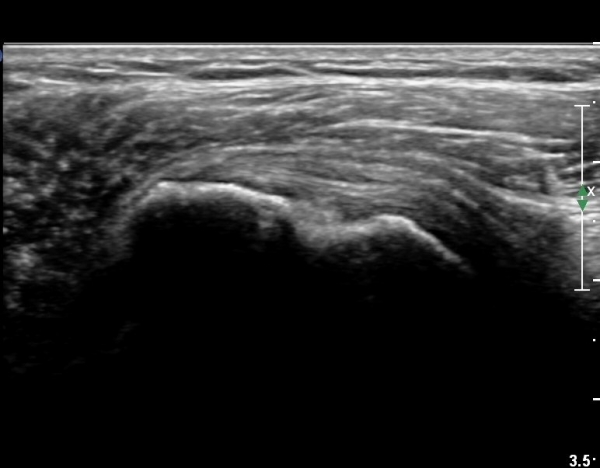

ȸÀü±Ù°³°£°Ý(rotator cuff interval) Ⱦ´Ü¸é°Ë»ç¿¡¼­ ÀÌµÎ¹Ú±Ù°Ç ¿ÜÃø¿¡ ±Ø»ó°ÇÀÌ °üÂûµÇÁö ¾Ê°í

´ë°áÀý Ç¥ÃþÀÇ »À°¡ ¿ïÅüºÒÅüÇÏ°Ô º¯ÇÏ¿´´Ù(±×¸² 1, 2)

ÀÌ´Â ½ÉÇÑ Ãæµ¹ÁõÈıºÀÇ °á°úÀ̰í ȸÀü±Ù°³ ÆÄ¿­À» °­·ÂÈ÷ ¾Ï½ÃÇÏ´Â ¼Ò°ßÀÌ´Ù.